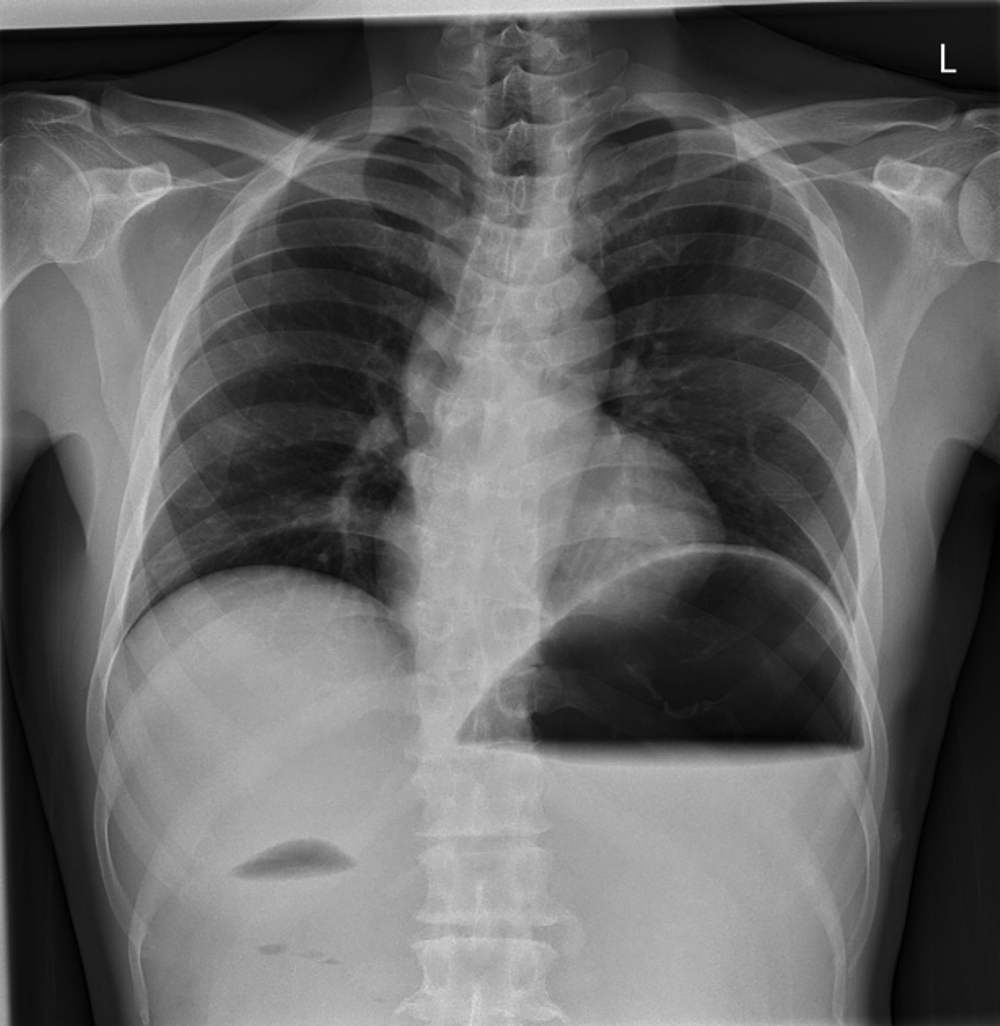

58yo male with abdominal pain and vomiting.